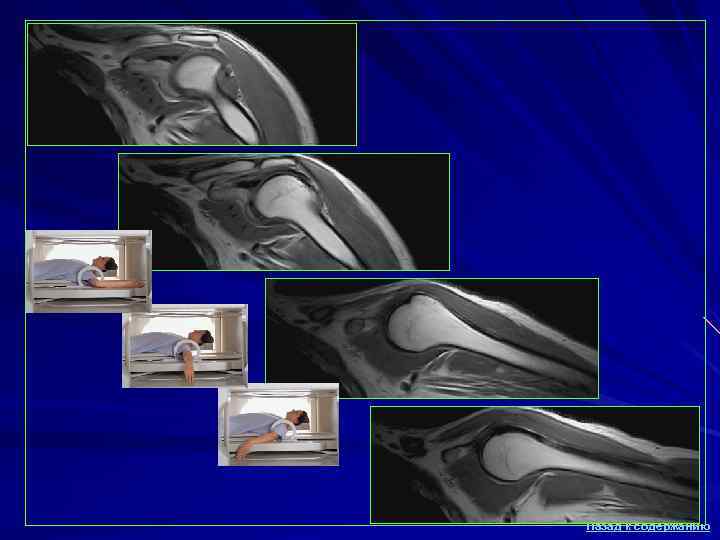

МРТ в травматологии и ортопедии Визуализации мягко-тканных структур (внутрисуставных связок, менисков, синовиальных складок) Патологические процессы, связанные с увеличением содержания жидкости (отек, инфильтрация, разрывы, контузии), представляются яркими (гиперинтенсивными) на Т 2 -взвешенных изображениях на фоне исходно низкой интенсивности сигнала от связок, менисков и сухожилий (структур с низким содержанием протонов). С появлением МРТ практически отпала необходимость в выполнении контрастной артрографии, а в отличие от ультразвукового исследования МРТ позволяет выполнить комплексную оценку как мягких тканей, так и губчатой кости при меньшей степени оператор- зависимости метода. Использование импульсных последовательностей с подавлением сигнала от жира (в т. ч. входящего в состав желтого костного мозга) позволяет выявлять зоны контузии (посттравматического отека) в губчатой кости. Назад к содержанию

Ограничения МРТ Длительность исследования и спокойное, неподвижное состояние пациента для получения качественных изображений, что определяет необходимость седации у беспокойных пациентов или применения анальгетиков у пациентов с выраженным болевым синдромом. Данная проблема усугубляется необходимостью пребывания пациента в неудобном нефизиологичном положении при некоторых специальных укладках (например, при исследовании плечевого сустава у крупных пациентов). Боязнь замкнутого пространства (клаустрофобия), в особенности у пациентов со склонностью к развитию истероидных реакций. Однако, во многих случаях эту проблему можно решить с помощью объяснения необходимости и важности диагностики, подробного разъяснения характера исследования, демонстрации устройства МР- томографа , легкой седации. Также для пациентов с клаустрофобией существенной психологической поддержкой является нахождение рядом врача или родственника на протяжении исследования. Вместе с тем, выраженная клаустрофобия является абсолютным противопоказанием для обследования методом МРТ. Назад к содержанию